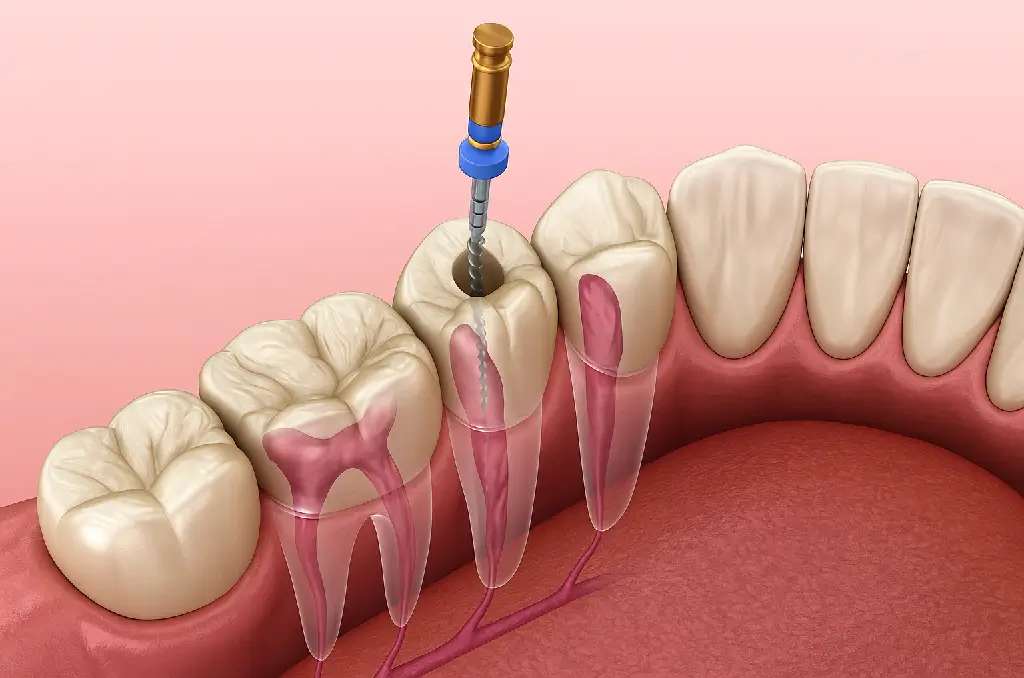

- Temizleme: Dişin iç kısmındaki enfekte pulpa çıkarılır, kök kanalları özel aletlerle temizlenir.

- Doldurma: Kanallar, özel dolgu materyalleriyle kapatılarak yeniden enfeksiyon oluşması önlenir.